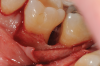

Fig 1. Tooth No. 19 at presentation, buccal view.

Figure 1

Fig 2. Tooth No. 19 at presentation, occlusal view. Note the thickness of the soft tissue and width of keratinized tissue.

Figure 2

Fig 3. Distal probing depth of 10 mm at tooth No. 19.

Figure 3

In the case presented, a 56-year-old healthy nonsmoking male patient, diagnosed with periodontitis stage III, localized, grade B, had been under care in a private practice periodontal office (RAL) for 25 years. He had a history of good compliance with his treatment (full-mouth plaque score <20%). During the COVID-19 pandemic, the patient missed three supportive periodontal therapy (SPT) visits over a year, resulting in periodontal breakdown interproximal between teeth Nos. 18 and 19 (mandibular left second and first molars, respectively). At his most recent periodontal maintenance visit, significantly increased periodontal probing depths of up to 10 mm with bleeding on probing were noted (Figure 1 through Figure 3). The periapical radiograph revealed a deep, narrow three-wall intrabony defect at the distal aspect of tooth No. 19, with class I buccal furcation involvement (Figure 4). According to the periodontal risk score (PRS),15 formerly known as the Miller-McEntire periodontal prognosis index, the tooth prognosis at the patient's initial examination was "good" (score = 5), taking into account that he was unaware of his hemoglobin A1C (HbA1c) levels. This scoring motivated the patient to be tested, and his follow-up HbA1c was <6%, thus reducing his PRS to 3, which was considered "excellent," as the PRS target goal for regenerative procedures is a score of <5.15